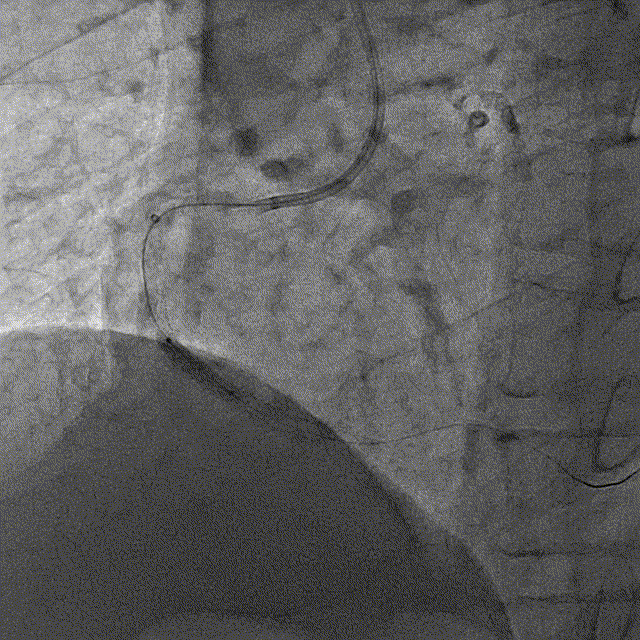

冠脉内介入治疗